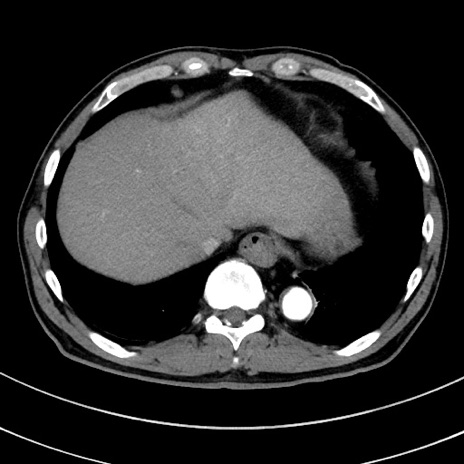

症例8(横断像)

【症例】 60歳代男性

【主訴】 黒色吐物

【現病歴】 4日前から嘔気自覚、2日前の朝食後にも嘔気あり、自分で手で嘔吐反射起こし嘔吐したところ血が混ざっていたため受診。

【既往歴】 5年前汎発性腹膜炎を伴う急性虫垂炎で手術、高血圧、前立腺肥大症、高脂血症

【身体所見】 腹部正中に手術癩痕あり 腹部平坦・軟圧痛なし膨満感あり

【データ】WBC 8400、CRP 4.54